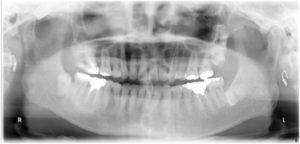

治療後の写真です。気になっていた前歯のデコボコが治りかみ合わせも安定しています。

図4(治療後)

図5(治療後レントゲン)

上の犬歯の後ろの歯を抜歯して治療しましたが、治療後のレントゲンをみても親知らず以外異常はありません。歯を支えている骨も健全です。